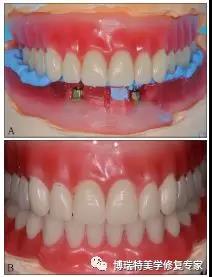

口内试戴杆卡及全口义齿(图7A、B),拍摄X线片检查杆与种植体平台的密合性(passive fit)(图7C),将基台种植体连接并加力至25 N·cm,完成最终修复(图7D)。

图7 最终修复效果 A:全口义齿;B:固位卡组织面观;C:X线片检查杆卡的被动就位,左侧未旋入基台螺丝,右侧旋入基台螺丝;D:正面微笑照